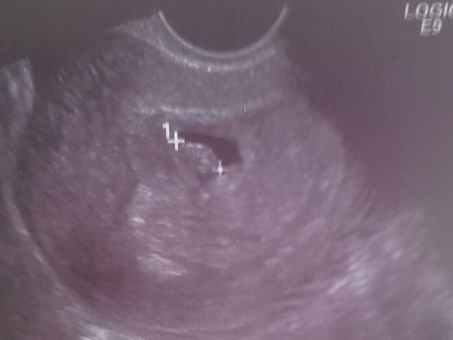

С первого визита к врачу и по наст.вр. набрала всего 600 гр., токсикоз мучал сильно с 12 по 19 неделю, в связи с чем бывалые пророчили мне девочку, хотя мы с мужем и так знали, что будет девченка, но всё же достоверно данный факт подтвердился на втором скрининге, пройденном в 19 недель. Пошли в частную клинику, попали к хорошему специалисту, налюбовались с мужем на нашу крошку. Показатели все в норме!